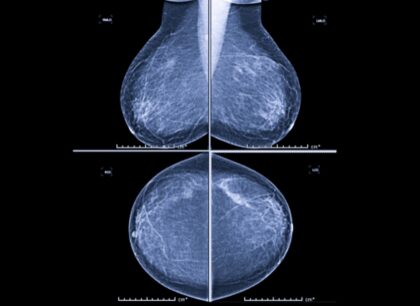

Lekári pri hodnotení mikrokalcifikátov sledujú viacero znakov, napríklad ich veľkosť, tvar, hustotu, rozloženie v prsníku či to, ako sa menia v čase. Práve tieto informácie pomáhajú určiť, či ide o bežný a neškodný nález, alebo o zmenu, ktorú treba podrobnejšie vyšetriť.

„Mikrokalcifikáty môžu byť v úplne skorom štádiu viditeľné len na mamografii, často ide o zmeny veľké len niekoľko milimetrov. Práve preto je mamografické vyšetrenie také dôležité a nenahraditeľné. Väčšie zmeny môžu byť neskôr viditeľné aj na ultrazvuku,“

vysvetľuje MUDr. Alexandra Bieliková, lekárka rádiológie AGEL Mammacentra sv. Agáty.